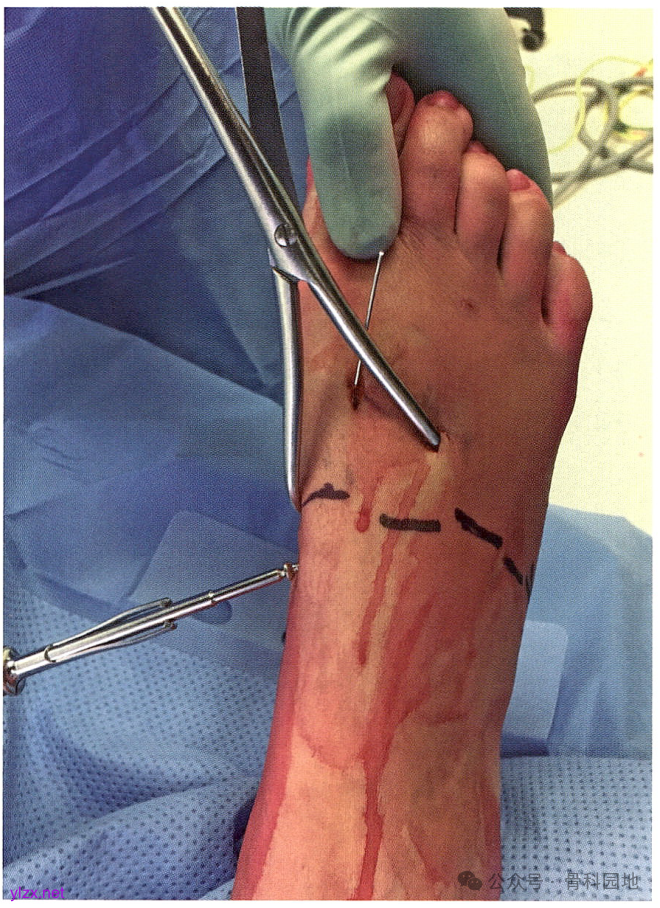

然后用点式复位(Weber)钳和手法复位第3TMT 关节。待第3TMT 关节复位后,经关节钻人1枚克氏针。

在第1、第2 和第3TMT 关节解剖复位并用克氏针临时固定后,从内侧楔骨向第2MT基底拧入“Lisfranc”螺钉。

完成第1、第2TMT关节的最终固定。

由于4 mm 骨皮质螺钉比 3.5 mm 螺钉或空心钉更坚固且更不易折断,所以建议使用4mm 骨皮质螺钉。但 3.5 mm 螺钉或空心钉对于小体格患者可能是足够的。如果使用空心钉,可以穿过克氏针拧人空心钉;但如果使用实心螺钉,只能从之前固定的克氏针旁边拧人。完成螺钉固定TMT关节,并用C臂机透视确认位置合适后,去除克氏针。